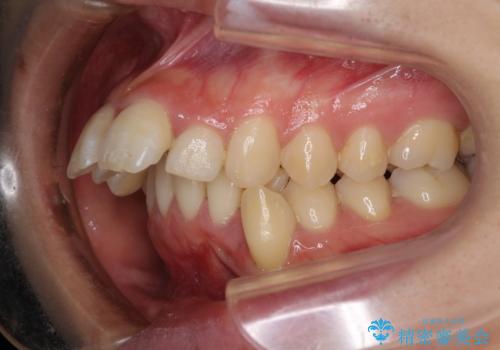

- 口元がひどく突出するくらいの上顎前突を気にして来院された患者様です。

舌の突出癖が顕著で、上顎歯列は完全なV字型となっている状態でした。

下顎歯列にも八重歯があり、上下左右の第一小臼歯4本を抜歯して、ワイヤー装置にて矯正治療を行うこととしました。

どこまで口元の突出感を改善できるのか不安でしたが、舌のトレーニングをしっかりと行ってくださり、我々も驚くほど劇的に改善することができました。